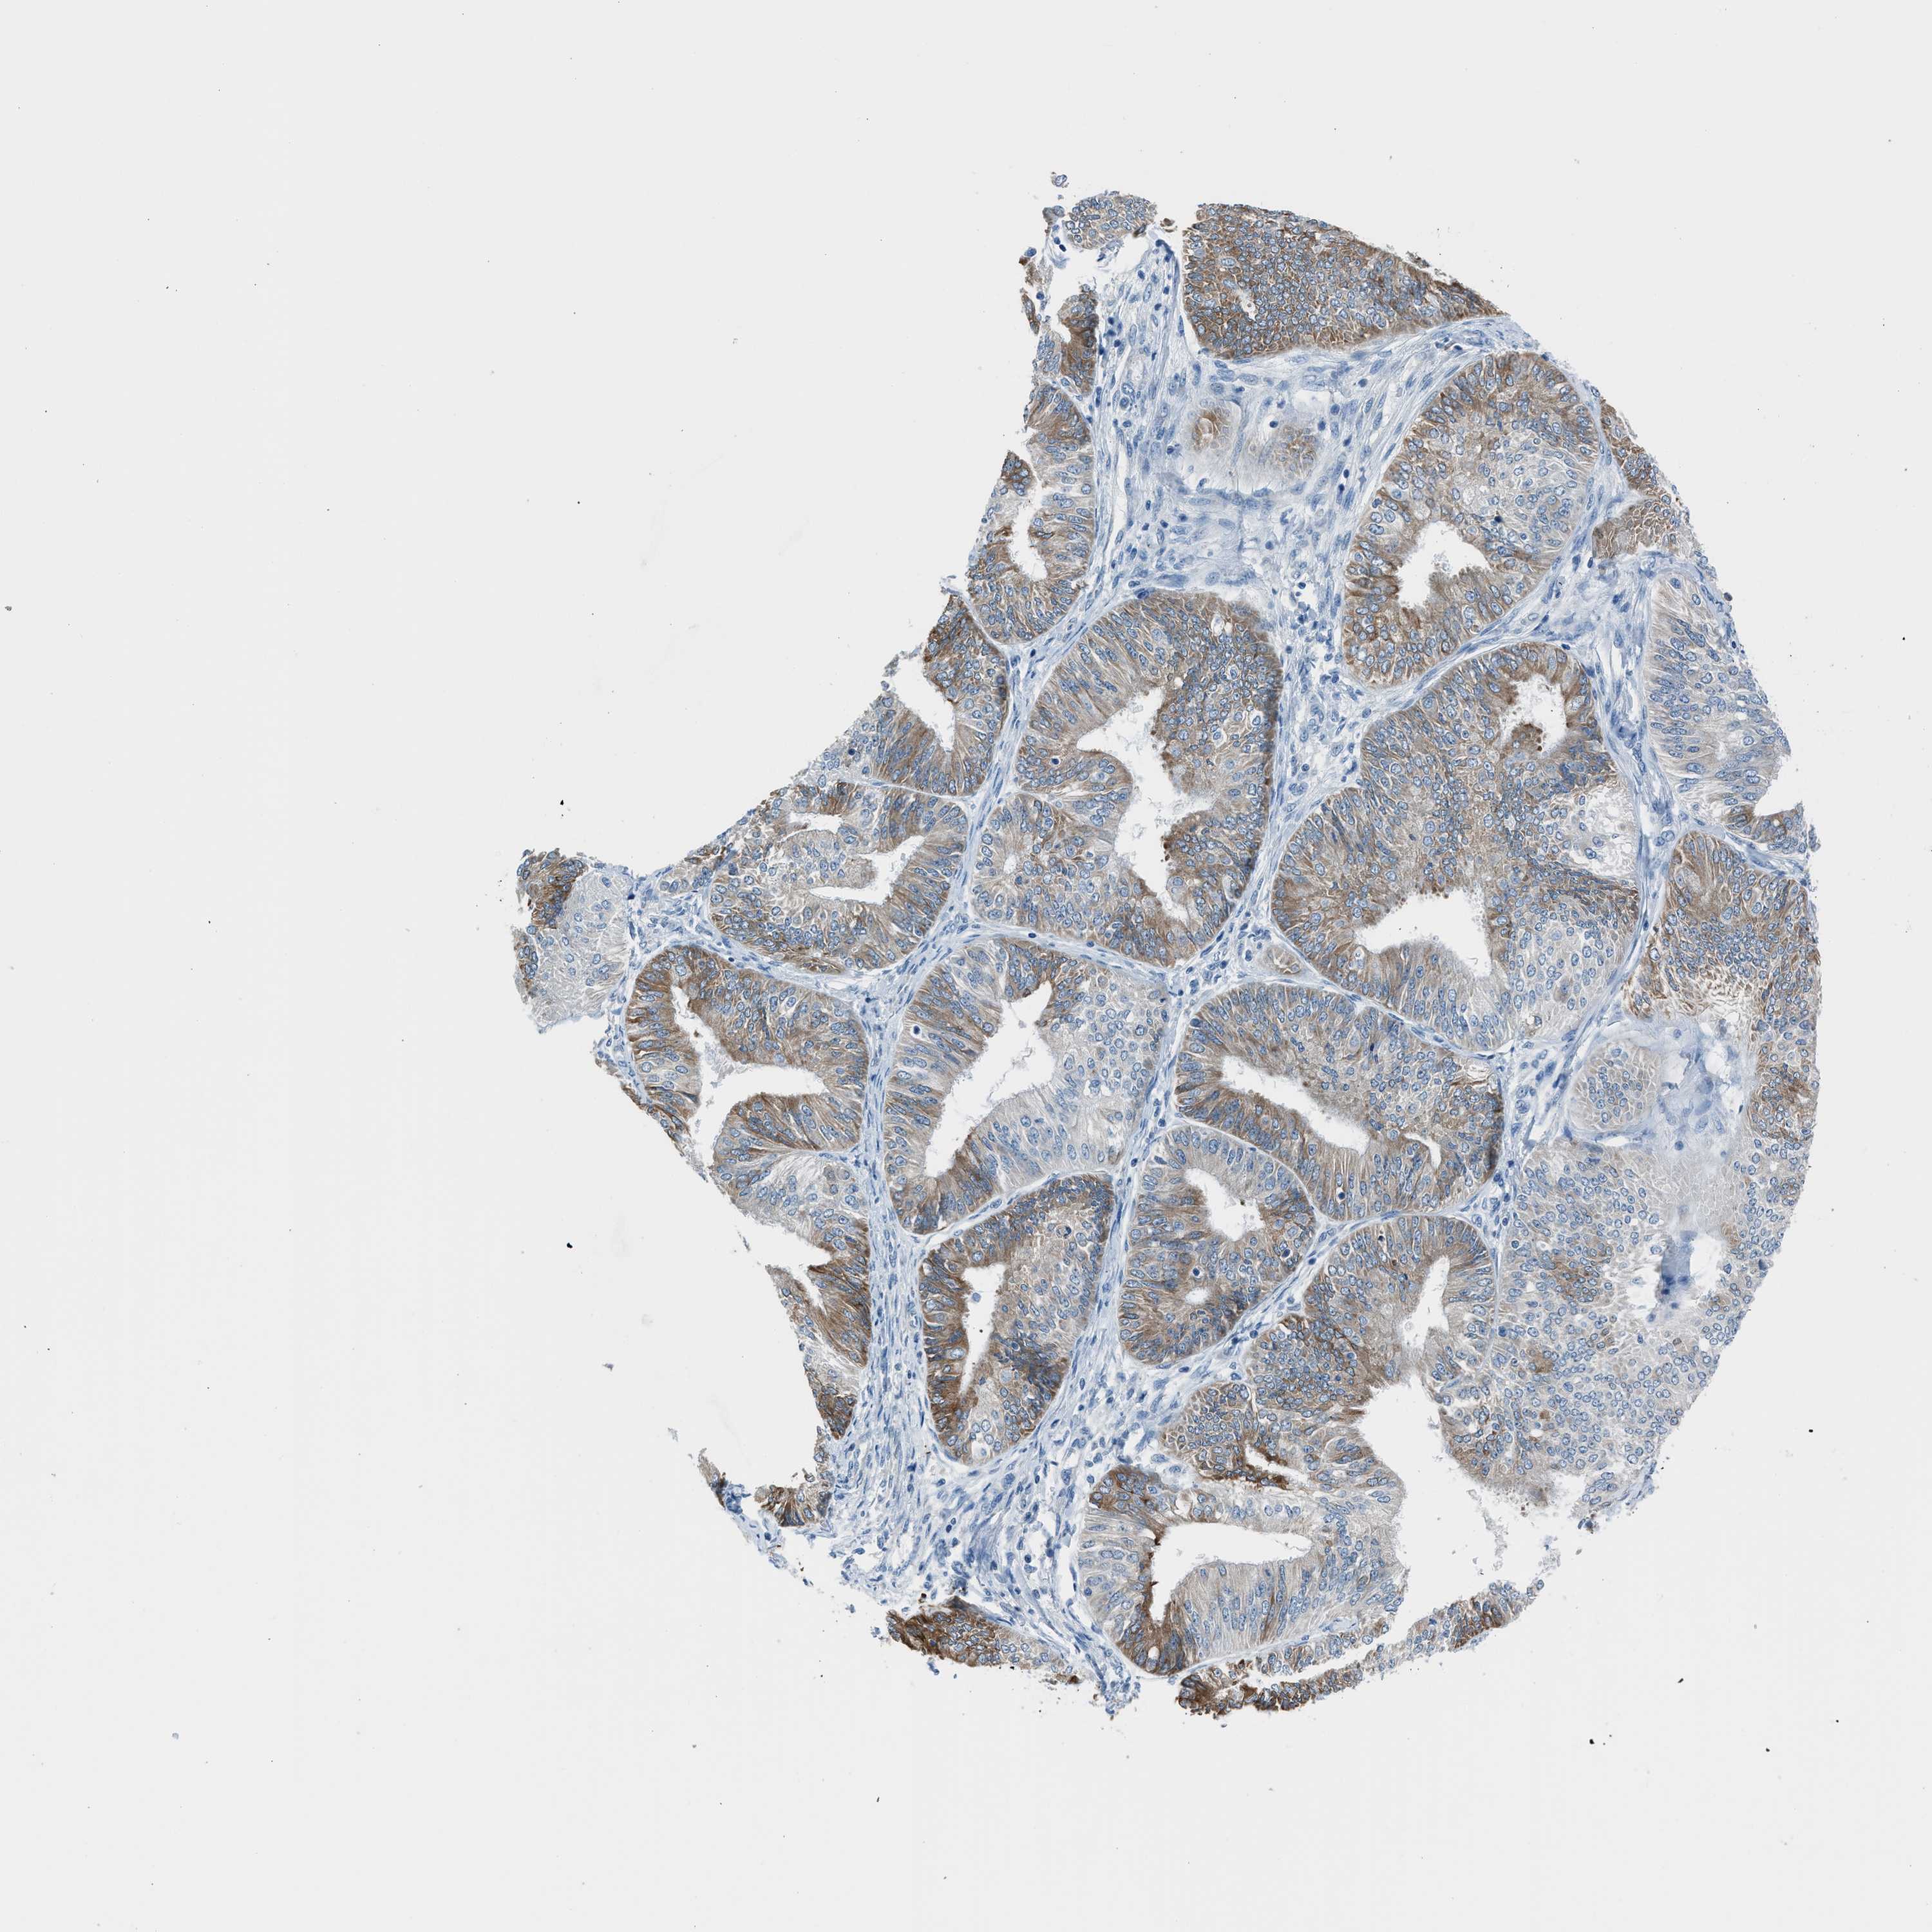

ENDOMETRIAL CANCER - Protein expressioni

A mouse-over function shows sample information and annotation data. Click on an image to view it in a full screen mode. Samples can be filtered based on level of antibody staining by selecting one or several of the following categories: high, medium, low and not detected. The assay and annotation is described here.

Note that samples used for immunohistochemistry by the Human Protein Atlas do not correspond to samples in the TCGA dataset.

Antibody stainingi

Antibody staining in the annotated cell types in the current human tissue is reported as not detected, low, medium, or high, based on conventional immunohistochemistry profiling in selected tissues. This score is based on the combination of the staining intensity and fraction of stained cells.

Each image is clickable and will lead to virtual microscopy that enables deeper exploration of all samples and also displays staining intensity scores, fraction scores and subcellular localization as well as patient and tissue information for each sample.

Antibody HPA016812

Staining

High

Medium

Low

Not detected

Intensity

Strong

Moderate

Weak

Negative

Quantity

>75%

75%-25%

<25%

None

Location

Nuclear

Cytoplasmic/membranous

Cytoplasmic/membranous,nuclear

Adenocarcinoma, NOS